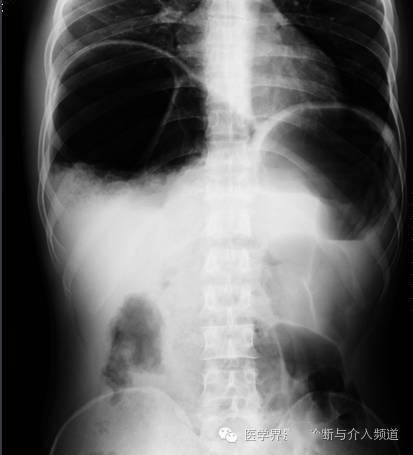

气腹(膈下游离气体)

同一患者前-后坐位的胸片所示右膈下(箭头)游离气体,证实了气腹的诊断